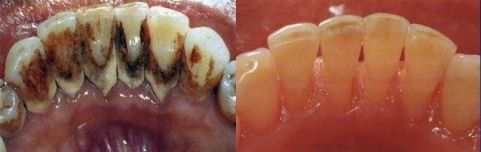

治疗前/治疗后

有一名女士,刷牙时经常牙龈出血,有时候轻轻咬一口苹果,也会残留血迹,这让她十分担忧口腔健康状况,遂于近日来我院口腔科就诊。

口腔科主任、副主任医师侯少慧接诊,通过全面细致的口腔检查,结合临床经验,确诊为牙周炎。经过一系列牙周治疗后,患者牙龈出血得以显著改善。“没想到,在口腔科治疗以后,现在刷牙时再也不像以前那样总是出血了,真的很感谢医生。”她高兴地说。